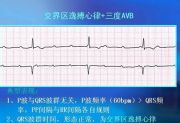

| 2021年7月26日 (一) 20:03 | 心脏电传导系统.jpg (文件) |  |

38 KB | Uploaded with SimpleBatchUpload | 3 |

| 2021年7月26日 (一) 20:03 | 心电图诊断.jpg (文件) |  |

61 KB | Uploaded with SimpleBatchUpload | 3 |